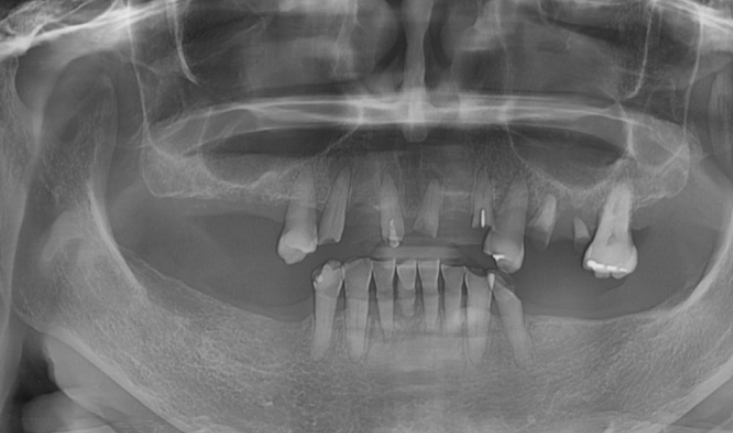

23.08.17 환자분을 처음 보았습니다.

어금니 치아는 위 아래 다 빠져있는 상황

남아 있는 치아 중에서도

문제가 많았습니다.

노랗게 삭아버렸거나

뿌리만 남아있는 치아도 많았는데요.

아래 치아의 경우 깨지고

치아가 뽑힌지 오래되어 잇몸뼈가 얼마 없는 상황이었습니다.